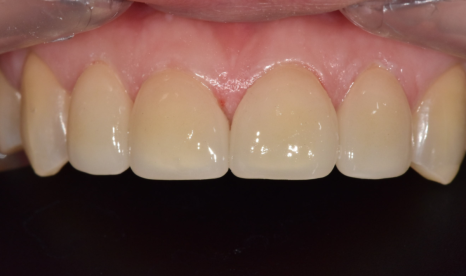

라미네이트를 통해

앞니 4개의 균형을 맞추고 나니,

단 며칠 만에 인상이 훨씬 단정해지셨습니다.

260108 / 260124

상실되었던 어금니 임플란트 역시

정확한 위치에 식립되어 튼튼하게 완성되었답니다.